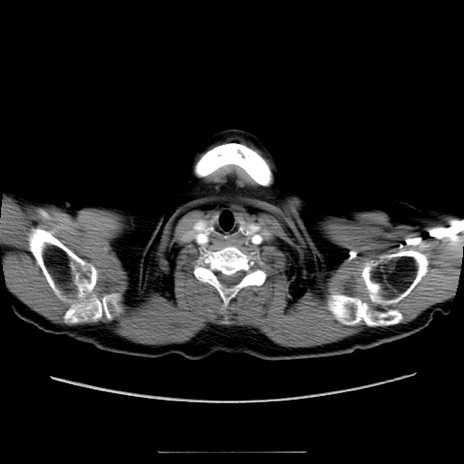

症例5(横断像)

【症例】70歳代女性

【主訴】お腹が張る

【現病歴】1週間くらい前から腹部膨満の自覚あり。昨日夜から増悪したため、本日救急外来受診。

【身体所見】意識清明、BT 36.5℃、BP 165/106mmHg、HR 80bpm、SpO2 98%、腹部:膨満、軟、自発痛・圧痛なし、触診にて不快感あり、腸蠕動音:減弱

【データ】WBC 12600、CRP 1.04